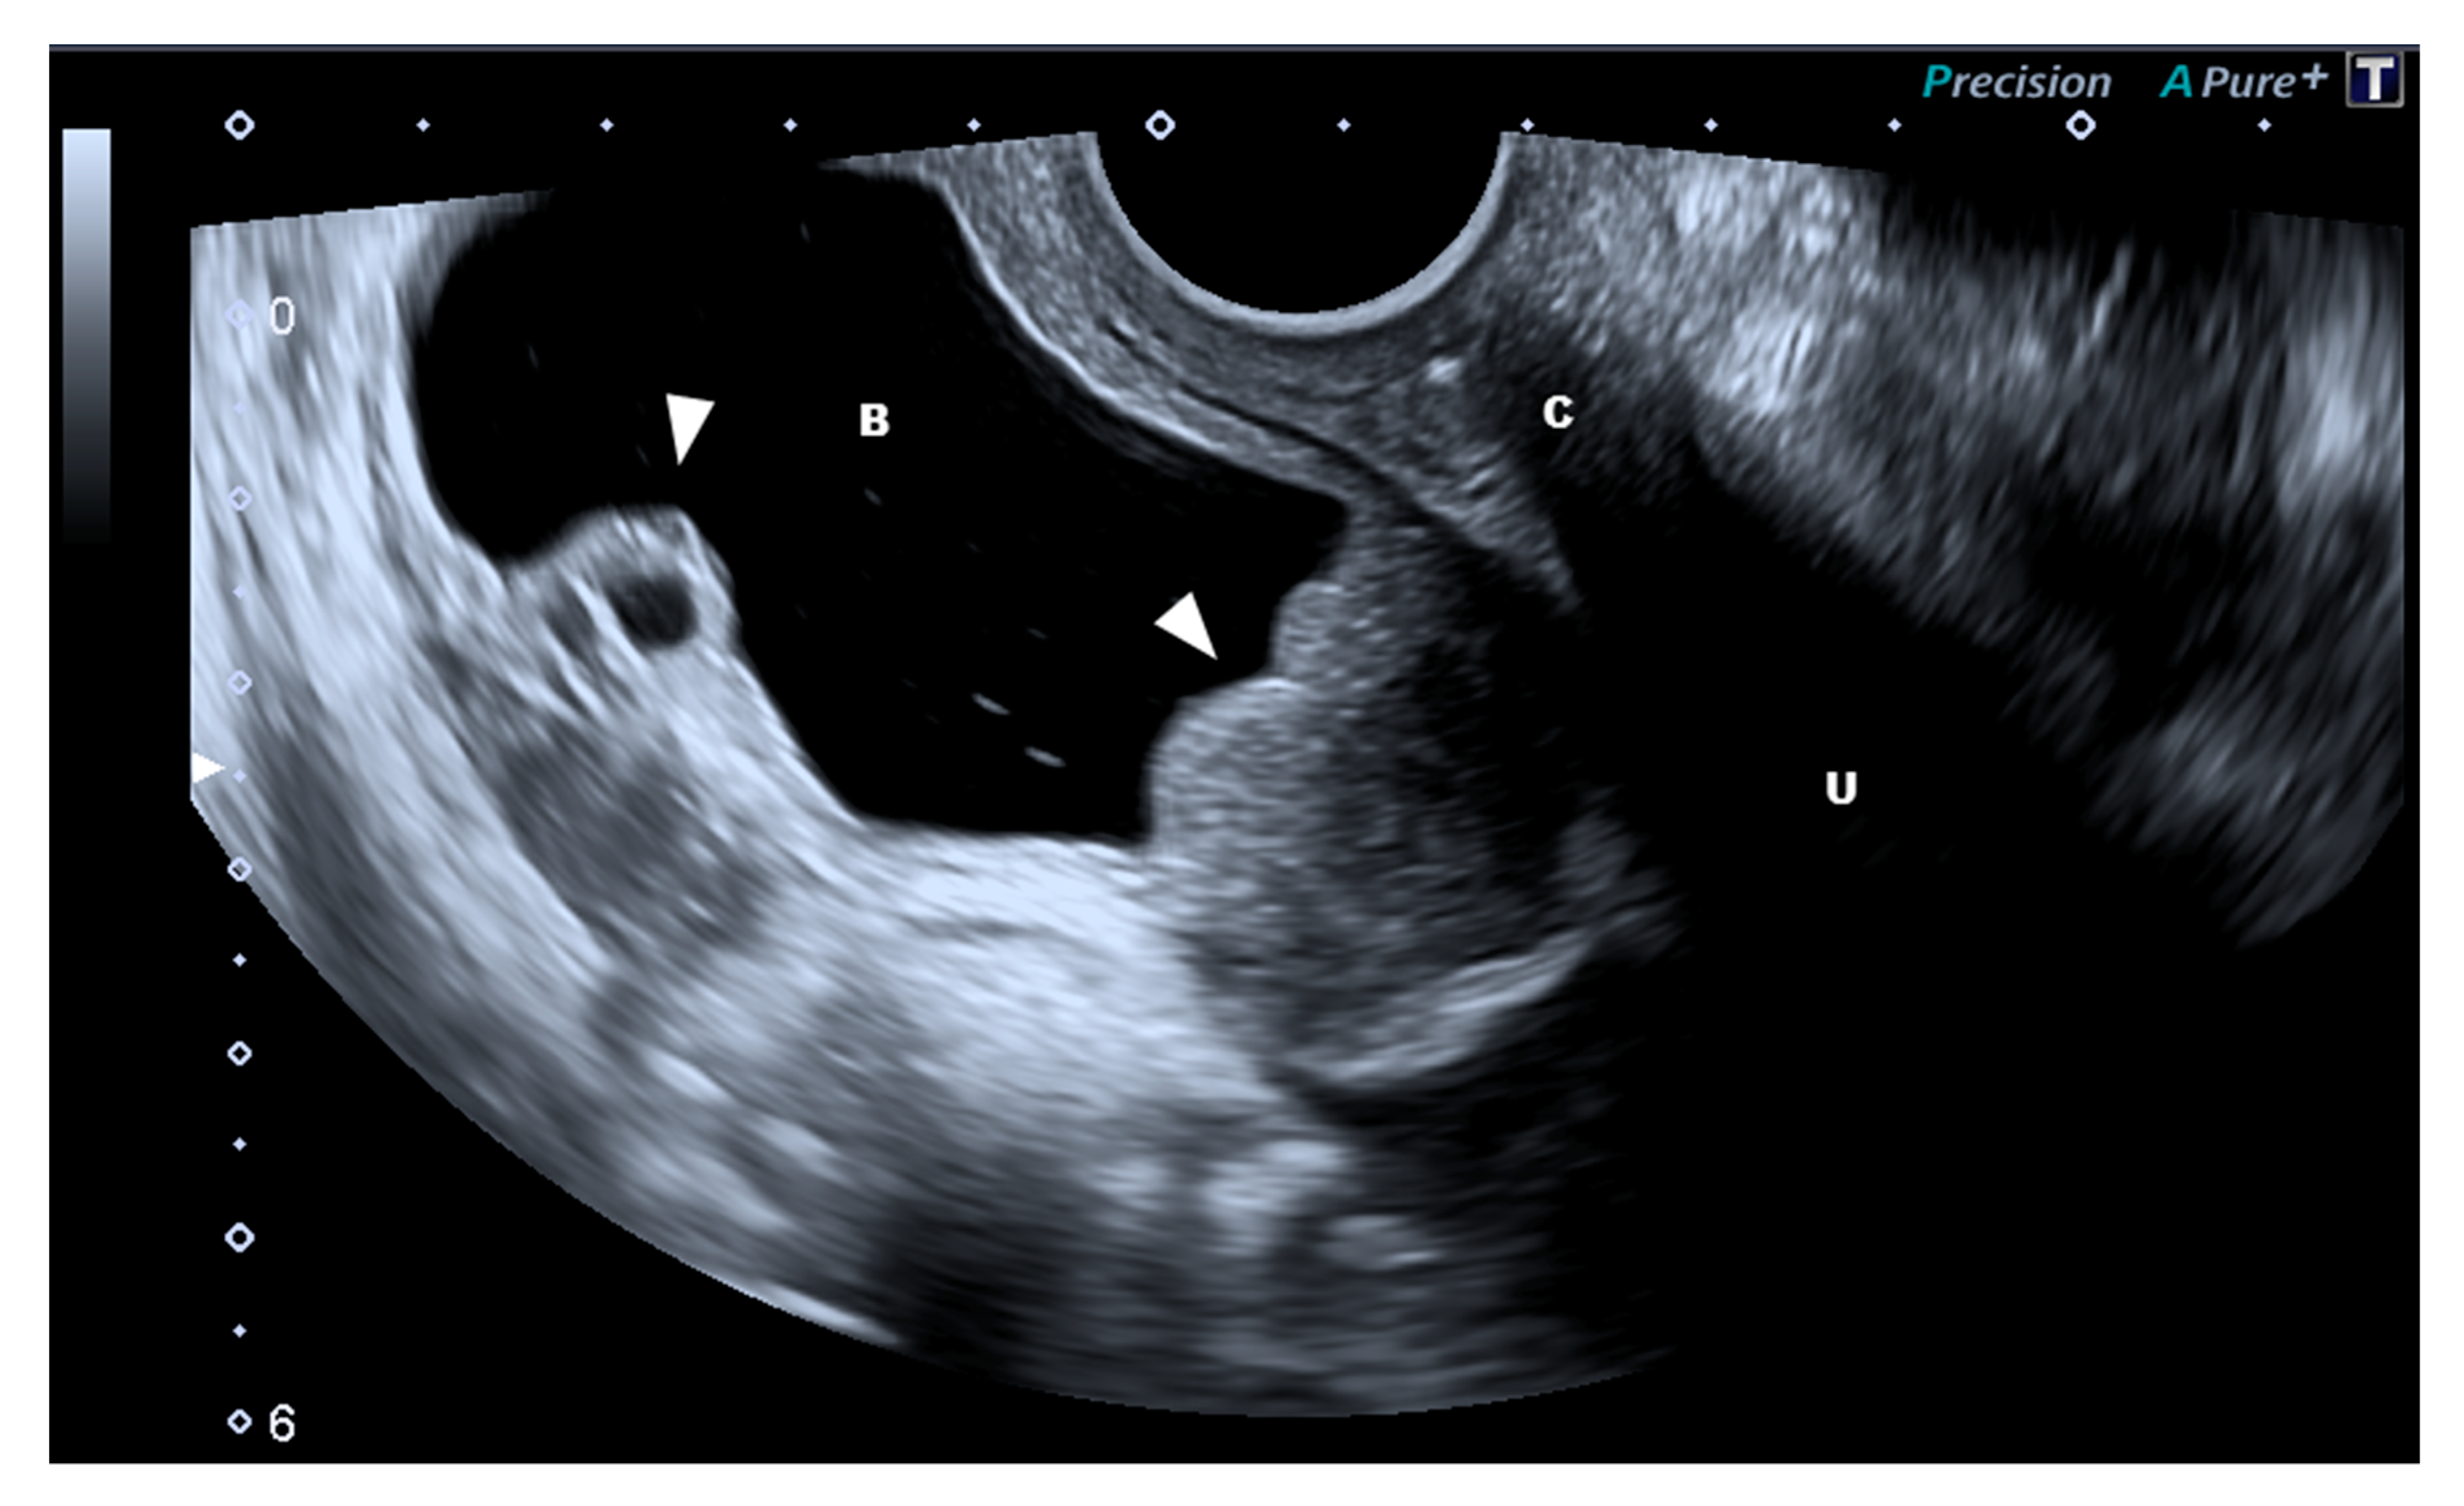

Figure 2.

Bifocal endometriosis of the bladder (arrow). The two lesions present different characteristics as the one on the right-hand side presents a typical solid aspect while the left one is a cystic endometriosis location. Abbreviations: B, bladder; C, cervix; U, uterus.